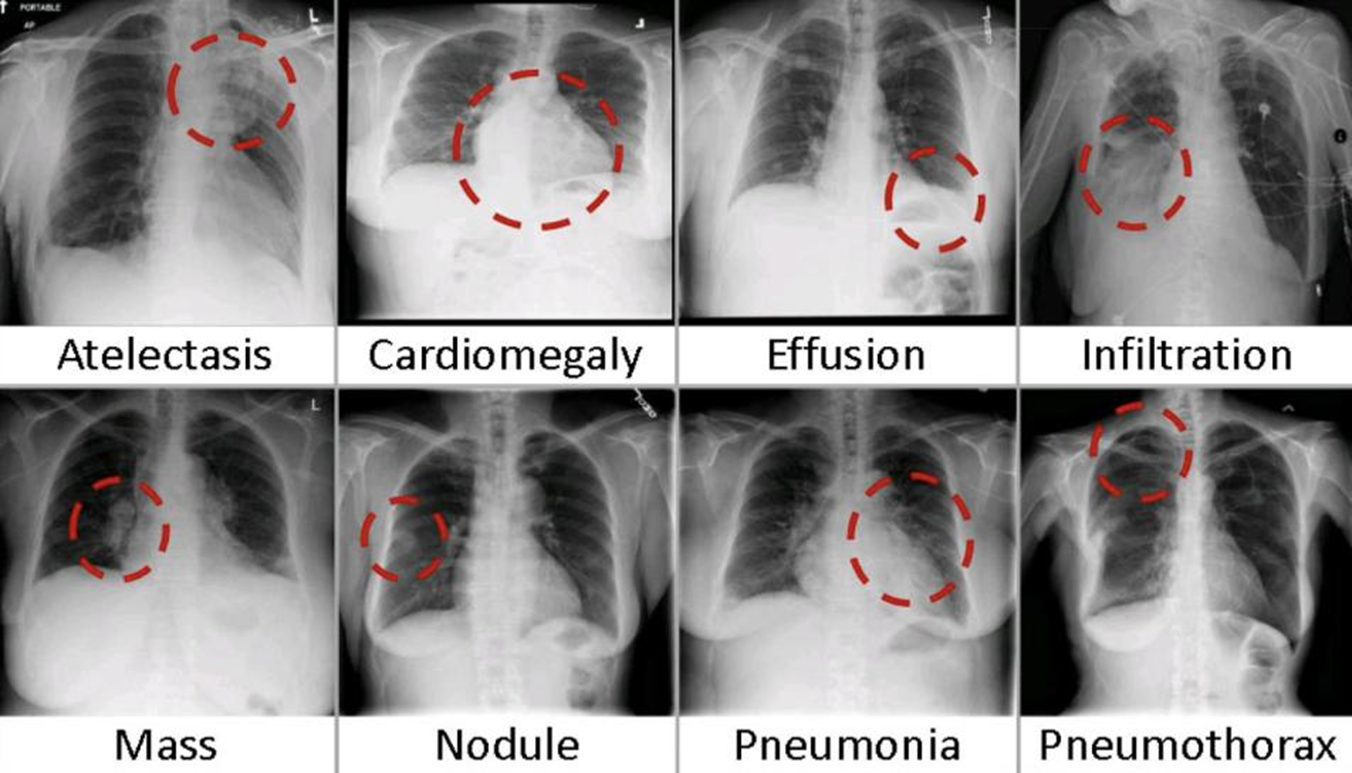

Multi-label은 Mutli-class와 다르게, 다중의 정답이 동시에 존재할 수 있는 것이다.

예를 들어, 폐에서 다중의 병변 및 증상을 찾아내야 하는 Task인 경우,

한 환자에서 폐렴, 폐결절, 심장비대증 등 다양한 증상이 동시에 존재할 수 있다.

위 그림의 예는 8개의 label이 존재하고, 각각은 독립적으로 동시에 발생한다.

따라서 이를 해결하기 위해서는 8개의 output을 sigmoid로 output을 해야하며,

동시에 label이 존재할 수 있으므로 binary_crossentropy를 활용하여야 한다.

model.add(Dense(8, activation='sigmoid'))

model.compile(loss='binary_crossentropy', optimizer=opt, metrics=['accuracy'])